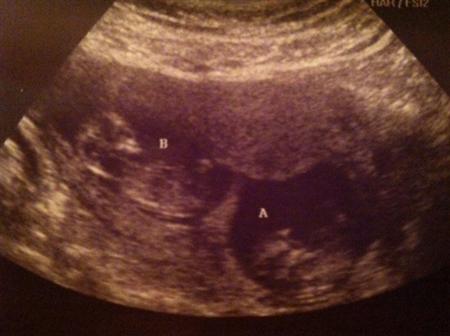

This pic (if it actually posts) is from my 11 weeks sono- and is the last pic I have of the 2 of them together... so it's the one I've decided to post. I hope it's ok that I posted on here instead of Pgy after IF... this is where most people look for updates from me (or so I've been told lol) and I hope that it will be a post of hope for those of you who are still on this journey Hope everyone has a great day! Image Attachment(s):

At 6 weeks DH and I went in and found 2 beautiful LO’s with heartbeats. <3 I was SO in love from that moment but really tried not to get too attached given our history… at 6 weeks 2 days I had some bleeding. Freaked out and went to Woodbury, to find their little hearts beating away…it’s AMAZING how much they grow in 2 days! Then at 8 weeks 4 days I had more bleeding and passed a large clot, and once again thought it was over… so back to Woodbury I went.

Thank God they were both still ok. Baby A had a low lying placenta that was right on my cervix, which was what they thought caused the bleeding. At this point I was put on bed rest and told to see Dr. Kofinas even though I wasn’t being released yet. At 9 weeks I went to see him and he determined that the clot that passed was actually from near baby B- we could see the dark spot on the sono, but everything was still ok. I was put on bed rest again …for weeks.

I’ll spare you the rest of details. I am SO totally in love with and in awe of them. I was fortunate enough to have a sonogram every week during the first trimester between all of my drs. I’m still amazed at how much they grow in such a short amount of time!!

As of today I’m 19 weeks and 1 day, and so far, so good. We had our partial anatomy scan yesterday and both babies measured right on target and seem to be doing well. I am still very nervous, but taking it one day at a time… I know that was one major hurdle and now in I think 4 more weeks we will have the full anatomy scan, so I will hold my breath for that one!